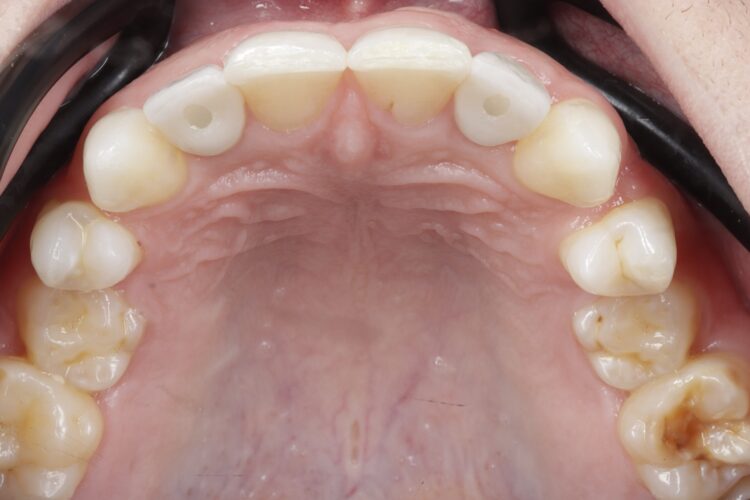

After completing orthodontic treatment, the patient attended a workup appointment, which included a CT scan, intraoral scans and pre-surgical photos and measurements.

Implant surgery (May 2023)

The implant surgery was performed in May 2023 and was filmed live as part of a surgical demonstration for the delegates on a guided surgery course being run by the Fitz Fahey Academy. Implants were placed in the UR2 and UL2 spaces with simultaneous hard and soft tissue grafting. Following the surgery, the patient was provided temporary teeth and instructed to avoid putting undue pressure on the implants during healing.